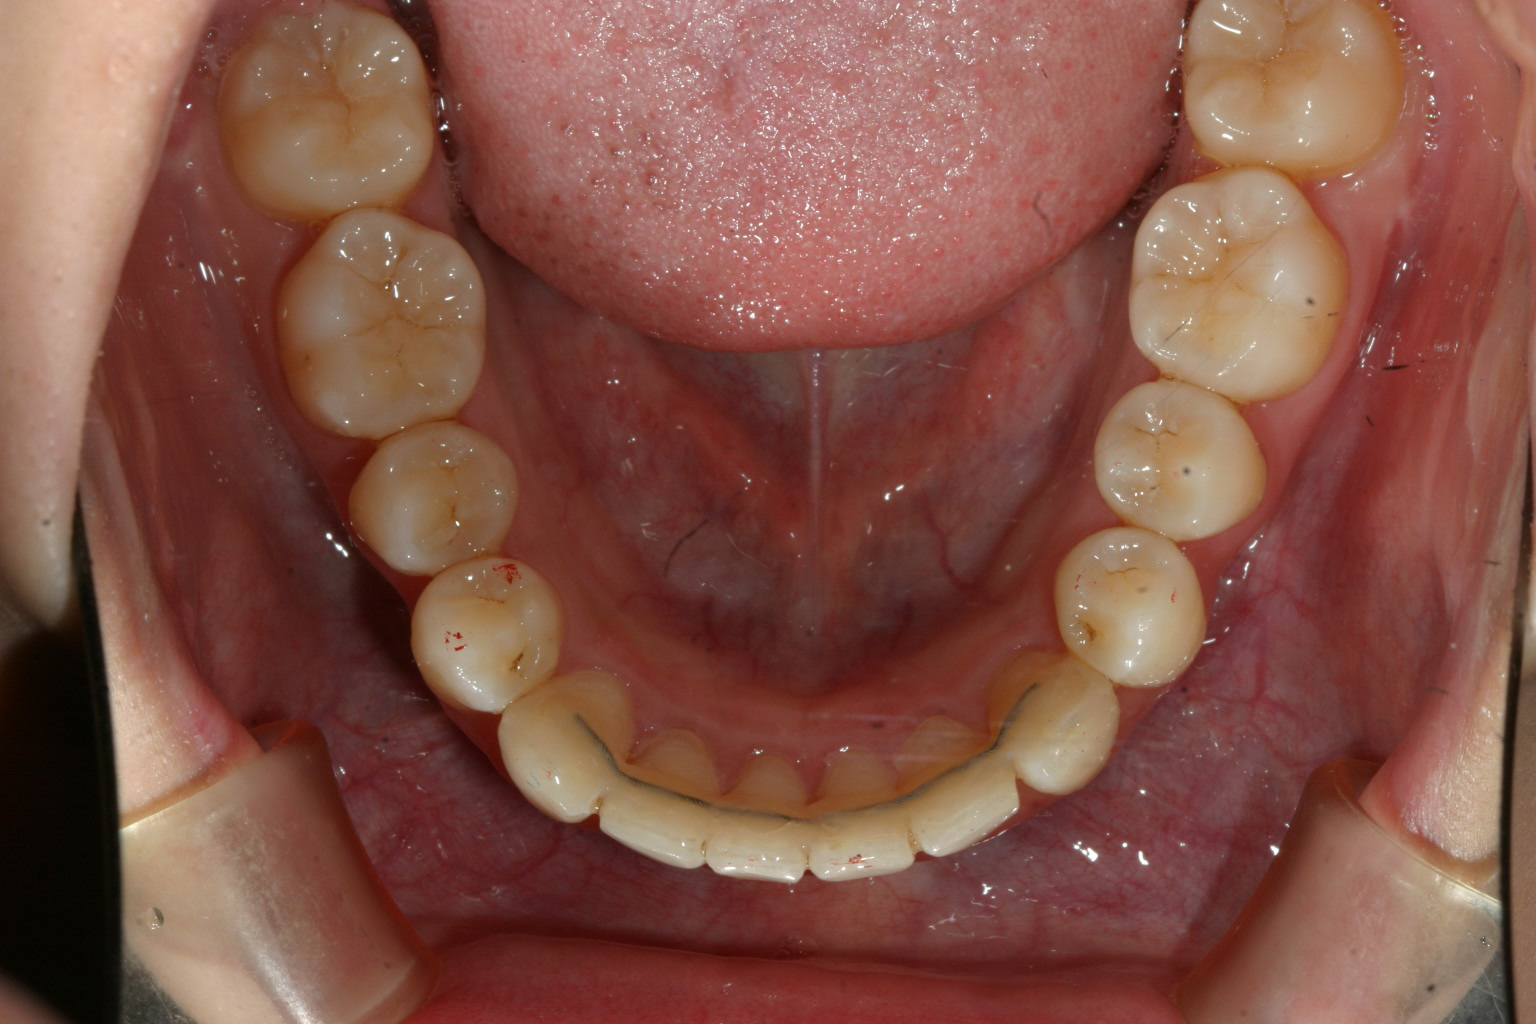

下顎もきれいに並びました。 最終リテーイナーとしてワイヤーで止めています。

下顎のアーチフォームもかなり悪いですがマウスピース矯正でもここまで綺麗に仕上げることが出来ます。